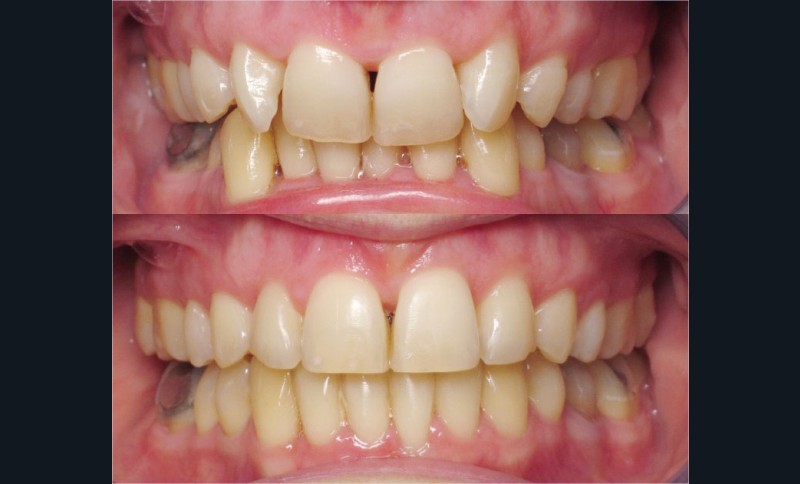

Nous lui avons donc proposé un traitement d’alignement avec maintien des 14 et 24 en position de 13 et 23 et optimisation du torque pour favoriser un développement des arcades et chercher à améliorer le sourire et le soutien labial.

La patiente donne son accord pour un appareillage Damon Insignia métal qui permet une individualisation complète des brackets dans les 3 sens de l’espace.

Les objectifs de traitement ont été remplis. Nous avons observé un excellent contrôle du torque et une absence de perte de l’occlusion postérieure grâce à la technique Insignia.